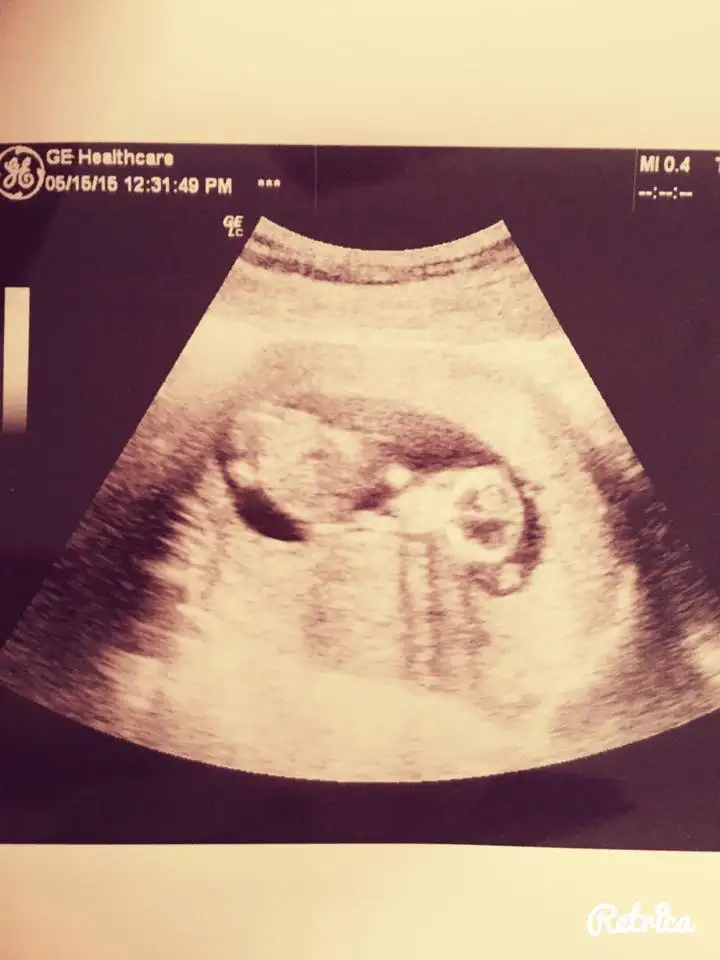

kızlar merhablar şimdi kontrolden geliyorum nolur bi bakın :))) sizce cinsiyetimiz ne ? 12. haftayı doldurduk bugün

Kızlar bana da yorum yapabilirmisiniz belli oluyor mu bilmiyorum ama açıkçası ben pek anlamıyor bebisim fotoda 12+4 haftalık tüp bebekle oldu sizce cinsiyeti nedir doktor ancak 16. Haftada söyleyebilirim dedi 12 haziranda bir daha ki kontrolüm çok merak ediyorum lütfen yardımcı olun